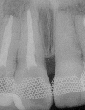

初診時の左上3初診時

2年後の左上3二年後